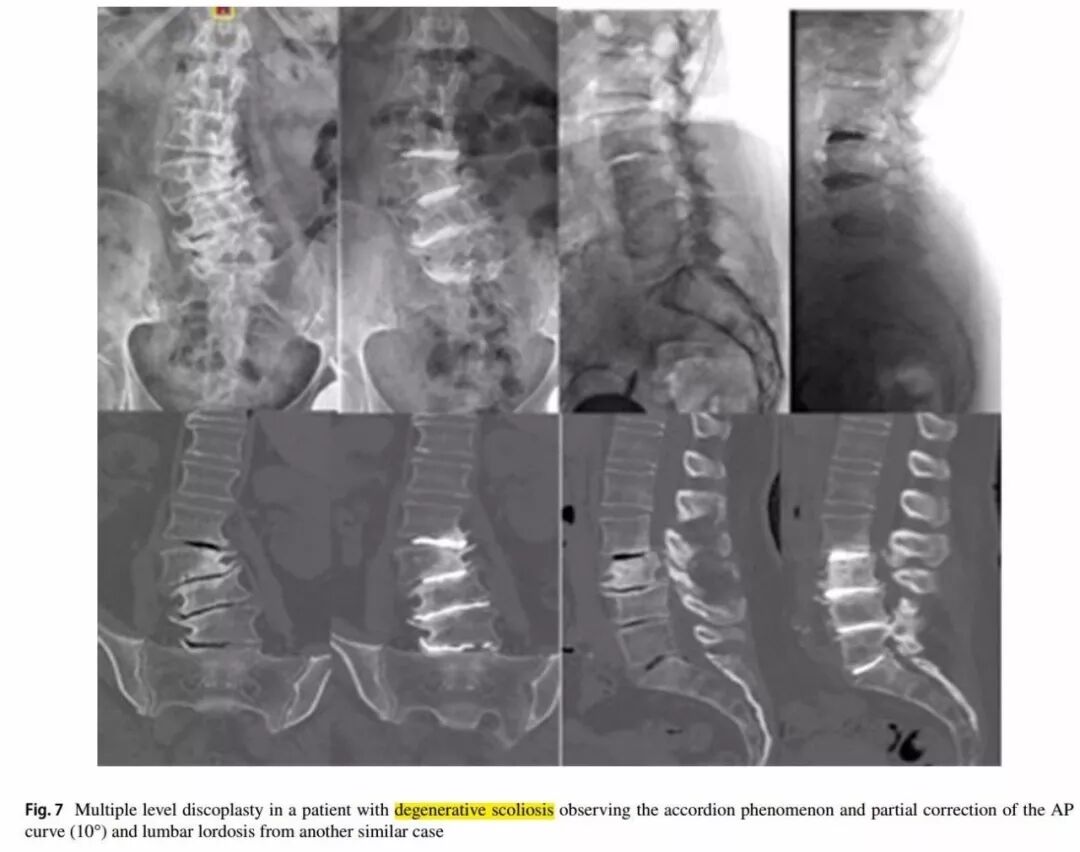

另一项来自阿根廷的technical note研究,详细的介绍经皮骨水泥椎间盘成形术的技术报道、适应症和禁忌症及优缺点。

适应症:存在机械性腰痛和椎间盘真空现象的老年患者,且症状与站立位或仰卧位X片、CT中椎间盘高度的变化有关,也称之为accordion phenomenon(手风琴现象)。1个或多个节段的脊柱畸形或退行性椎体滑脱且因高手术风险、不能耐受开放手术的患者。

-

禁忌症:严重骨质疏松症、严重畸形、肥胖等为相对禁忌症;感染和肿瘤为绝对禁忌症。

典型病例

一例78岁的老年患者,慢性腰痛1年(VAS 7分),活动后加重,卧床后减轻,严重影响生活质量,但无下肢放射痛,无四肢运动和感觉障碍。

术前影响资料可见退行性侧凸伴多节段椎间盘真空征。

典型的手风琴现象

左图为站立位X片,右图为仰卧位CT平扫。站立位负重时的椎间盘与仰卧位(不负重)椎间盘塌陷程度不同,且侧凸角度也不同(分别为25°和14°)。

术后情况

2例退变性侧凸患者术后比较